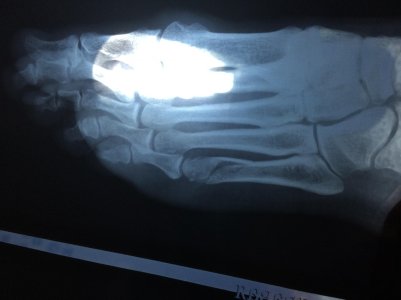

Здравствуйте. 21 марта оступилась и подвернула ногу. В итоге перелом 5 плюсневой кости без смещения. Наложили лангет. Продолжила наблюдаться у врача по месту прописки. Ногу не осматривали, снимки не делали, и первые снимки даже не посмотрели, пробыла в гипсе почти 5 недель, ногу не нагружала. 23 апреля на приеме у врача попросила, чтобы сделали рентген. Рентген сделали, но врач ничего не сказал о ноге. А врач, который описывал снимок в рентген кабинете, уточнял точно ли у меня перелом 5 плюсневой (то ли потому что все срослось, то ли снимок в гипсе не очень качественный, я не поняла). Я сама сняла гипс 25 марта (через 5 недель), потому что когда закроют больничный, снимут гипс надо будет сразу ехать в другой город на работу (это долго и на поезде) и я решила заранее начать разрабатывать ногу, немного ходить. В районе перелома побаливает. Это нормально? Мне вначале сказали, что трещина небольшая.

Скажите, пожалуйста, по первым снимкам от 22 марта в какой части у меня перелом, на сколько он серьезен? Я немножко переживаю, что я поторопилась снять гипс. Последний снимок от 23 апреля не получается хорошо сфотографировать.